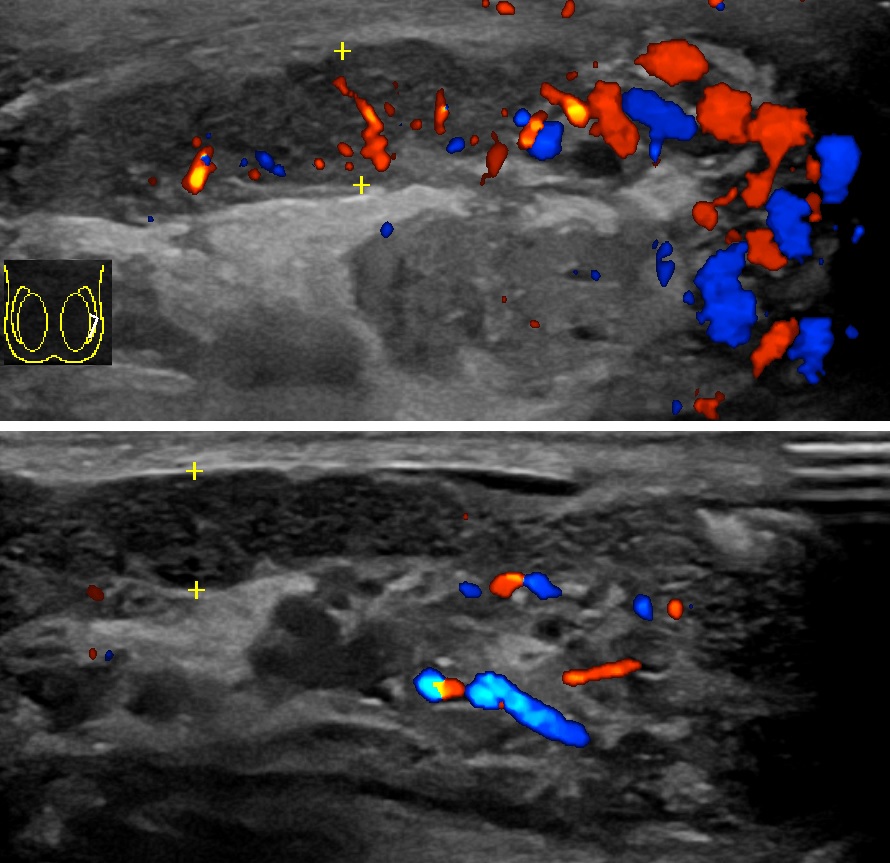

진단은 일반적으로 증상을 기반으로 한다.[1] 유사한 증상을 유발할 수 있는 질환으로는 고환 염전, 서혜부 탈장, 고환암 등이 있다.[1] 진단이 불분명한 경우 도플러 초음파 검사가 유용할 수 있다.[1]

정교한 의학 영상 기술이 개발되기 전에는 외과적 탐사가 표준 치료법이었다. 오늘날에는 도플러 초음파 검사가 일반적인 검사이다. 이는 혈류 영역을 보여주고 부고환염과 염전을 명확하게 구별할 수 있다. 그러나 염전 및 고환 통증의 다른 원인은 촉진만으로도 종종 확인할 수 있으므로, 일부 연구에서는 초음파의 유일한 실질적인 이점은 고환암이 없음을 환자에게 확신시키는 것이라고 제안했다.[10] 핵의학적 고환 혈류 검사는 드물게 사용된다.

정교한 의학 영상 기술이 개발되기 전에는 외과적 탐사가 표준 치료법이었다. 오늘날에는 도플러 초음파 검사가 일반적인 검사이다.[10] 이는 혈류 영역을 보여주고 부고환염과 염전을 명확하게 구별할 수 있다. 그러나 염전 및 고환 통증의 다른 원인은 촉진만으로도 종종 확인할 수 있으므로, 일부 연구에서는 초음파의 유일한 실질적인 이점은 고환암이 없음을 환자에게 확신시키는 것이라고 제안했다.[10] 핵의학적 고환 혈류 검사는 드물게 사용된다.